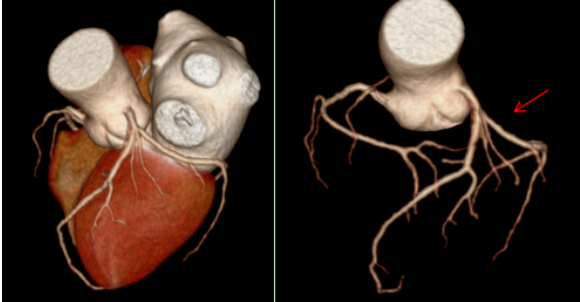

经过一系列检查,辽宁一脉阳光医学影像诊断中心医生通过冠状动脉CT血管成像(CCTA)发现,他的左冠状动脉前降支近端出现了中度狭窄,同时还伴有心肌桥的形成。这个结果,正是典型冠心病的表现。

在张大爷的病例中,CT影像清晰显示了他的左冠状动脉前降支近端有中度狭窄。前降支是冠状动脉中最重要的一支,负责左心室大部分血液供应。这里的狭窄,直接导致了他胸痛胸闷的症状。更特别的是,检查还发现了“心肌桥”,当心脏收缩时,心肌会压迫血管,进一步加重血流受限。这种结合了狭窄和心肌桥的情况,在老年患者中并不罕见,但也增加了诊断和治疗的复杂性。

从影像学角度看,CT冠状动脉成像是无创诊断的金标准之一。它通过三维重建技术,将冠状动脉的形态、狭窄位置和程度直观呈现出来。

在张大爷的检查中,医生利用宽体探测器CT获得了高质量的冠状动脉图像。图像清晰显示了狭窄的位置和程度,以及心肌桥的形态。这种技术的优势在于其高时间分辨率和空间分辨率,能够“冻结”心脏运动,避免运动伪影,从而提供诊断所需的精细解剖信息。此外,低剂量扫描技术的应用,还减少了辐射暴露,特别适合老年和体弱患者。

影像学不仅是诊断工具,更是评估预后的重要手段。通过CT,医生可以量化狭窄程度、评估斑块性质(如钙化斑块与非钙化斑块),并为后续治疗提供导航。